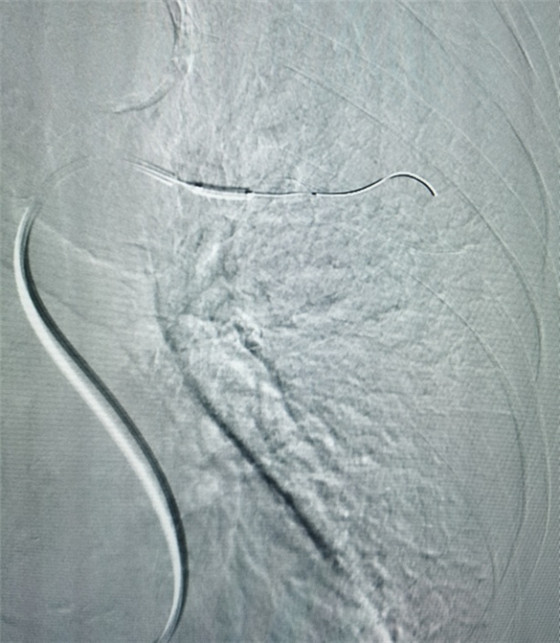

經(jīng)皮肺動(dòng)脈造影

經(jīng)皮肺動(dòng)脈栓塞導(dǎo)管碎栓溶栓術(shù)

經(jīng)綜合評(píng)估并與家屬充分溝通后,局麻下行肺動(dòng)脈造影,提示左肺動(dòng)脈主干及左肺下葉動(dòng)脈閉塞,立即予以經(jīng)皮肺動(dòng)脈栓塞導(dǎo)管介入碎栓溶栓術(shù)。在心內(nèi)科韋鋒主任、郭良玉主治醫(yī)師及成婷護(hù)師的默契配合下,爭(zhēng)分奪秒順利完成手術(shù)。術(shù)后即刻復(fù)查肺動(dòng)脈造影示左肺動(dòng)脈主干及左肺下葉動(dòng)脈恢復(fù)血流,生命體征穩(wěn)定,指脈氧恢復(fù)至100%。經(jīng)過(guò)精心治療與護(hù)理,目前患者已康復(fù)出院。